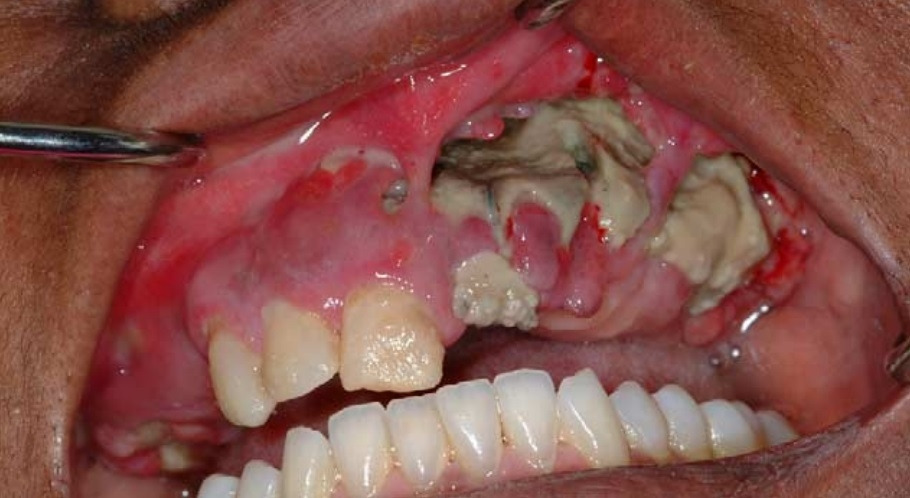

치과 치료 후 발생할 수 있는 무서운 부작용인 턱뼈괴사(ONJ, osteonecrosis of the jaw)가 골다공증약(비스포스포네이트)을 복용한 환자에서 생기는 것이다(*제목란 사진). 발치 후 상처가 아물지 않고 고름이 나오고, 턱뼈가 무너져 내려 치료가 매우 힘들고, 심지어 턱뼈를 잘라내는 경우도 있다 하니 끔찍한 일이다.

이런 주사약들은 경구약 문제인 위장장애는 피했지만 또 다른 문제가 생겼다. 주사 후 근육통, 관절통, 독감유사 증상이 흔히 나타났고, 심각한 부작용으로 턱뼈괴사의 빈도가 늘어난 것이다 (아래 사진).

SL Ruggiero et al. J Oral Maxillofac Surg 2004.

턱뼈괴사 보고가 처음 나온 건 2003년이었다. 골다공증약 장기사용 시 생길 수 있는 아주 드문 합병증으로 보고되었다 [6,7,8]. 하지만 2004년부터 많은 증례들이 연이어 발표되면서 턱뼈괴사에 대해 우려가 점점 고조되었다 [9,10,11,12,13,14,15,16].